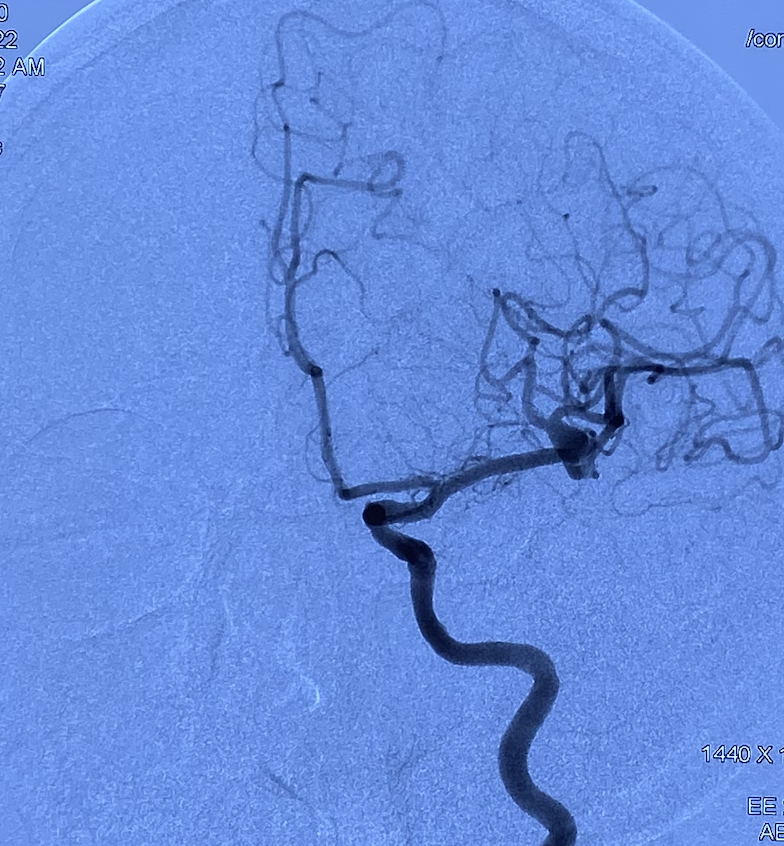

脑血管造影

DSA:右侧大脑中动脉瘤,形态不规则,夹层可能,瘤体可见分支血管,4.5mm×3.2mm,瘤颈5.8mm;远近端载瘤动脉直径分别为2.71mm、2.93mm。